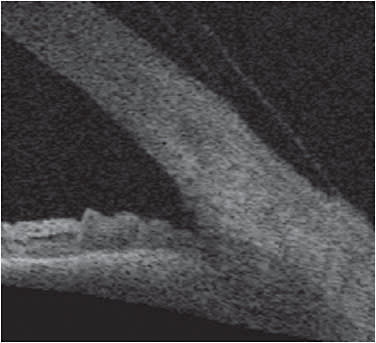

Optical coherence tomography (OCT) is also a great tool that can help evaluate clearance and edge alignment. OCT assessments of the anterior surface can be performed using a dedicated anterior segment OCT or an OCT that allows assessment of the posterior or anterior segment. While the cross-sectional images of the ocular surface are useful for estimating the sagittal depth of the eye, OCT instruments also allow practitioners to capture an image while a scleral lens is on the eye. Assessing clearance between the posterior surface of the scleral lens and the ocular surface can be performed by using calipers in the imaging software. Evaluating the toe up or toe down qualities of the scleral lens is easy when the edge of the lens is captured in the images (Figure 5). This is particularly useful when variations in edge lift are visible in different quadrants, making clear where a lens is not fitting the scleral contour well and modifications are needed. For example, it is easy to see a lens edge that is too steep, as it compresses the sclera. Ordering a flatter edge in the meridians in which this occurs can make a lens more comfortable for a patient.